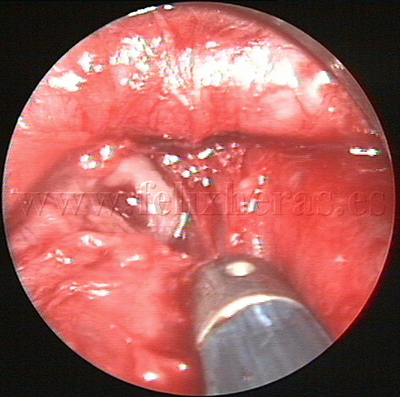

Linfoma cérvico-mediastínico

Biopsia por videomediastinoscopia